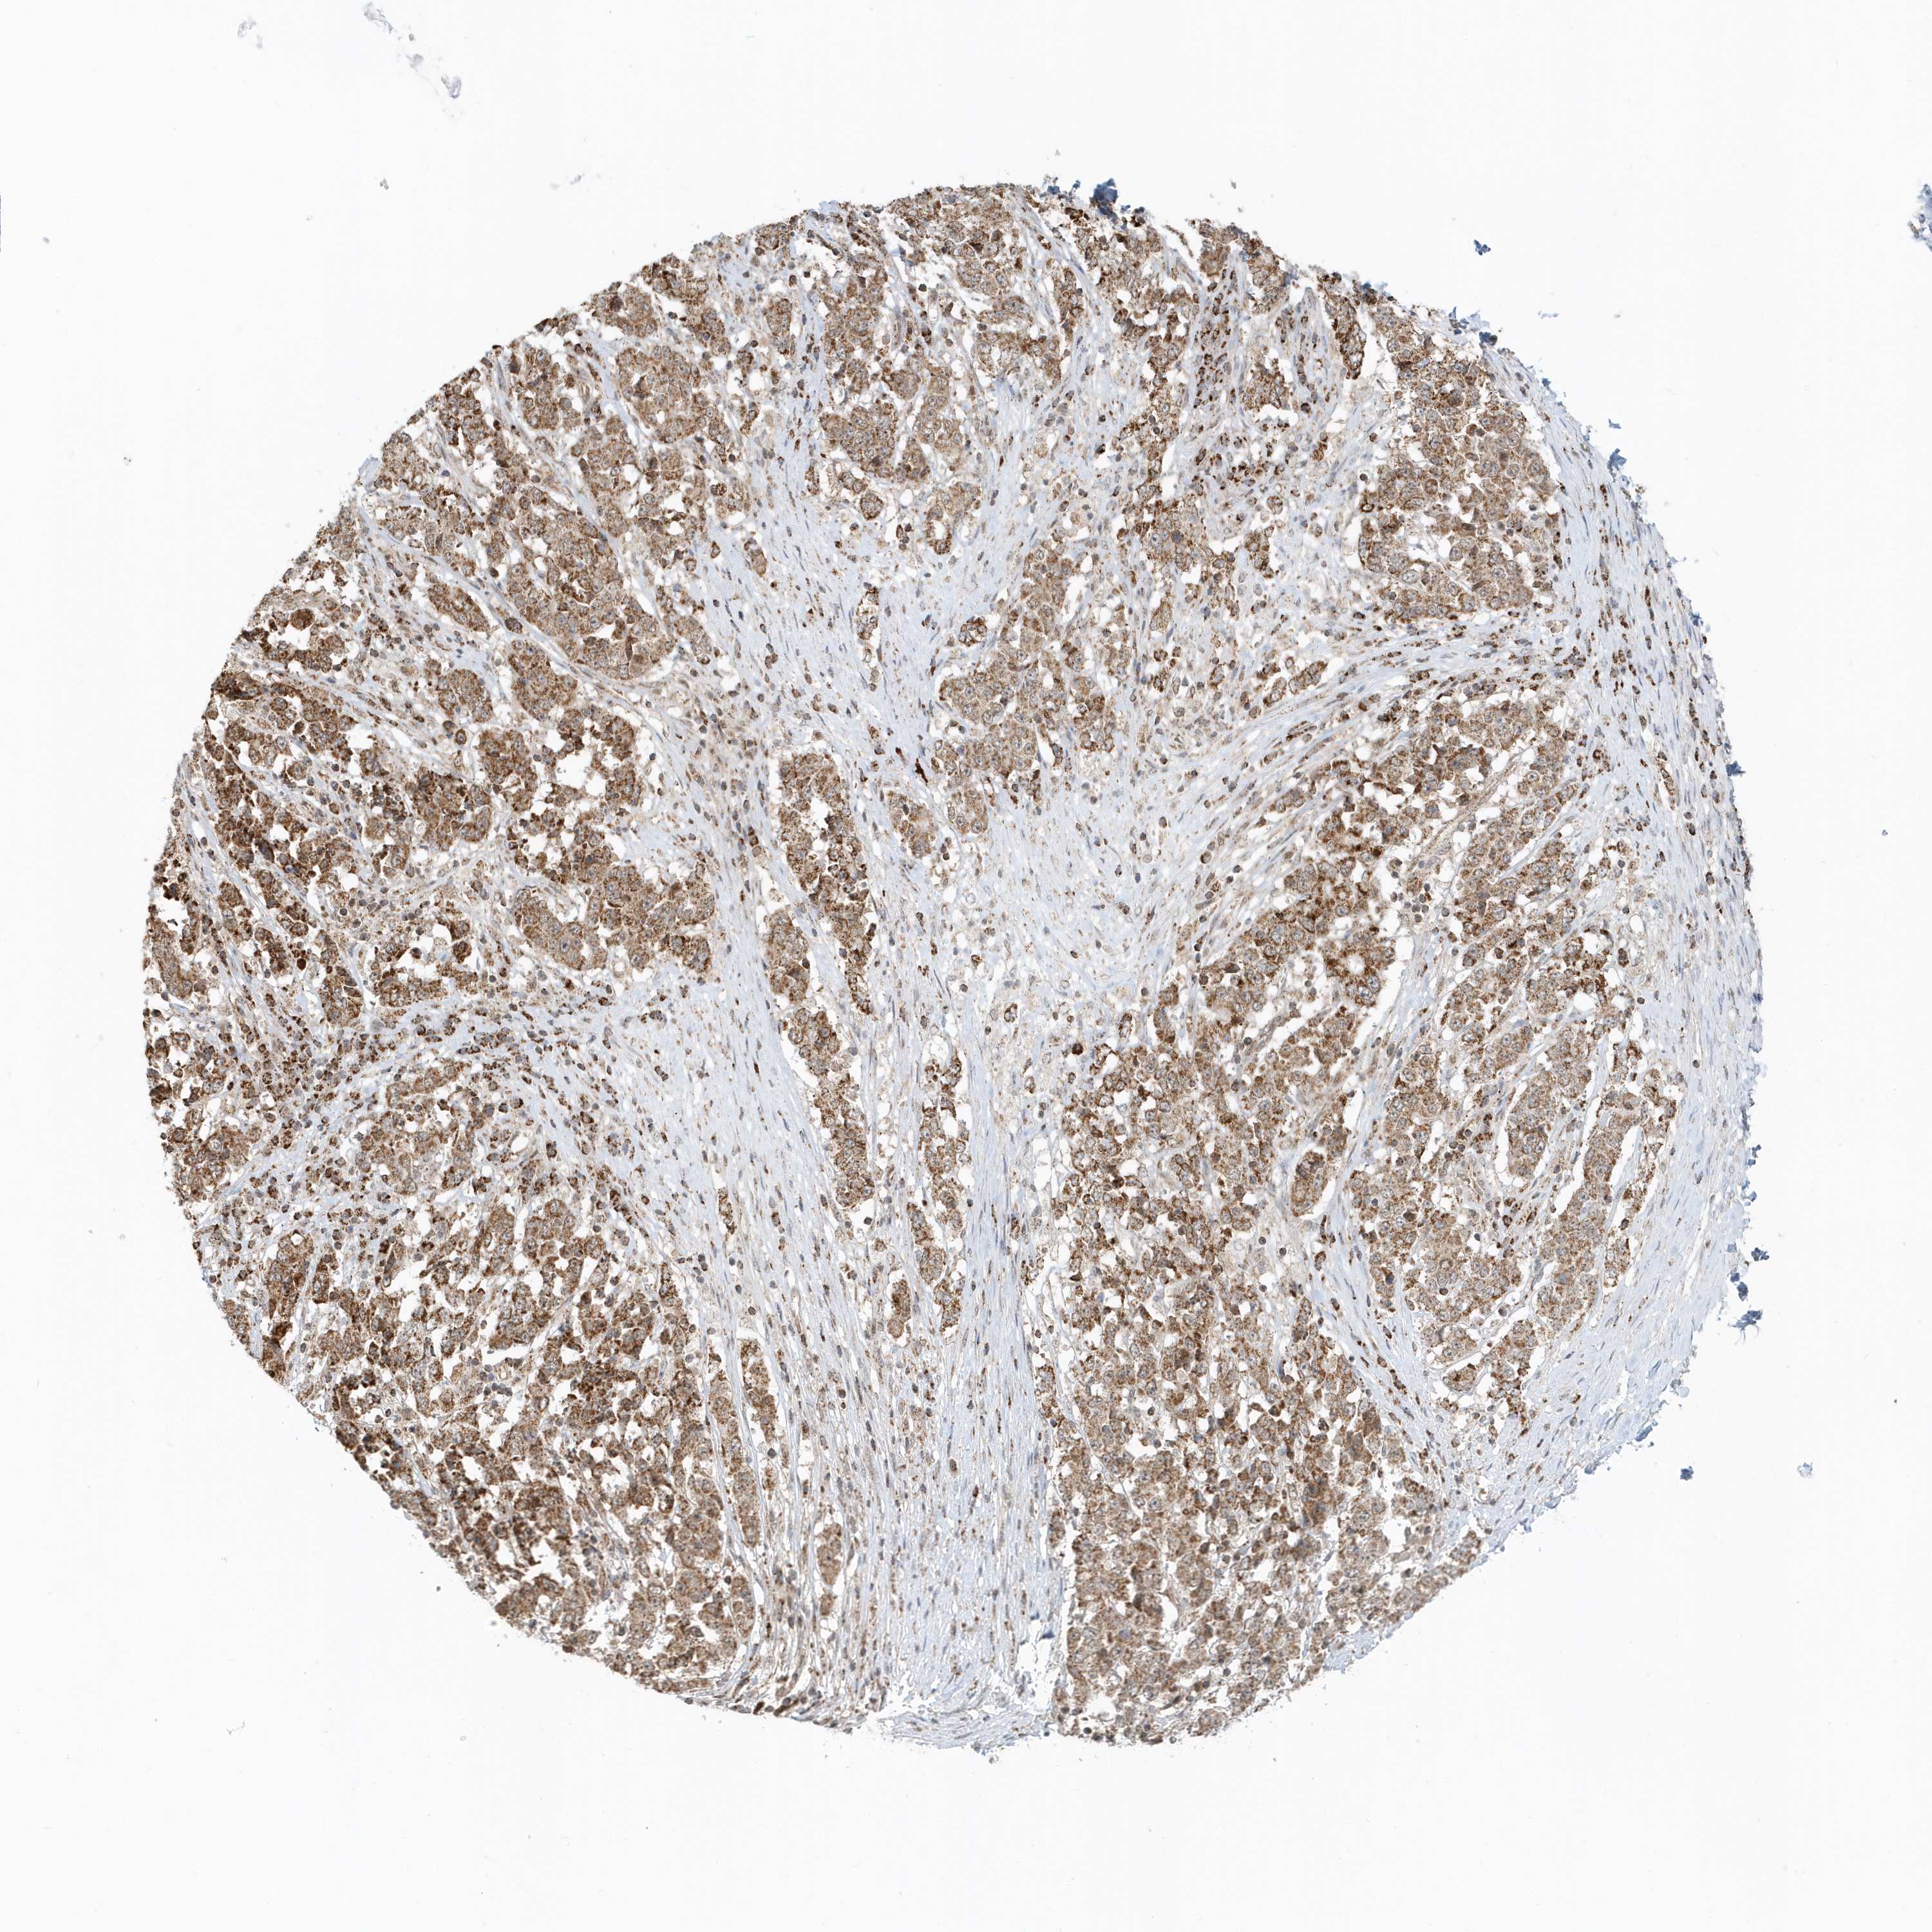

STOMACH CANCER - Protein expressioni

A mouse-over function shows sample information and annotation data. Click on an image to view it in a full screen mode. Samples can be filtered based on level of antibody staining by selecting one or several of the following categories: high, medium, low and not detected. The assay and annotation is described here.

Note that samples used for immunohistochemistry by the Human Protein Atlas do not correspond to samples in the TCGA dataset.

Antibody stainingi

Antibody staining in the annotated cell types in the current human tissue is reported as not detected, low, medium, or high, based on conventional immunohistochemistry profiling in selected tissues. This score is based on the combination of the staining intensity and fraction of stained cells.

Each image is clickable and will lead to virtual microscopy that enables deeper exploration of all samples and also displays staining intensity scores, fraction scores and subcellular localization as well as patient and tissue information for each sample.

Antibody HPA036921

Antibody HPA036922

Staining

High

Medium

Low

Not detected

Intensity

Strong

Moderate

Weak

Negative

Quantity

>75%

75%-25%

<25%

None

Location

Nuclear

Cytoplasmic/membranous

Cytoplasmic/membranous,nuclear

Adenocarcinoma, NOS